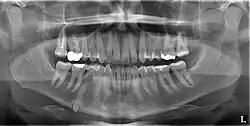

Classifications enable the oral surgeon to determine the difficulty in removal of the impacted tooth. [9] The primary factor determining the difficulty is accessibility, which is determined by adjacent teeth or other structures that impair access or delivery pathway. The majority of classification schemes are based on analysis on a radiograph. The most frequently considered factors are discussed below.

Angulation of tooth

Most commonly used classification system with respect to treatment planning. Depending on the angulation the tooth might be classified as:

Relationship of tooth to anterior border of ramus

This type of classification is based on the amount of impacted tooth that is covered with the mandibular ramus. It is known as the Pell and Gregory classification, classes 1, 2, and 3.[10]

Relationship of tooth to occlusal plane

The depth of the impacted tooth in relation to the adjacent second molar serves as the foundation for this type of classification. This was also given by Pell and Gregory and is known as the Pell and Gregory A, B, and C classification. Relationship to the occlusal plane A-C classes